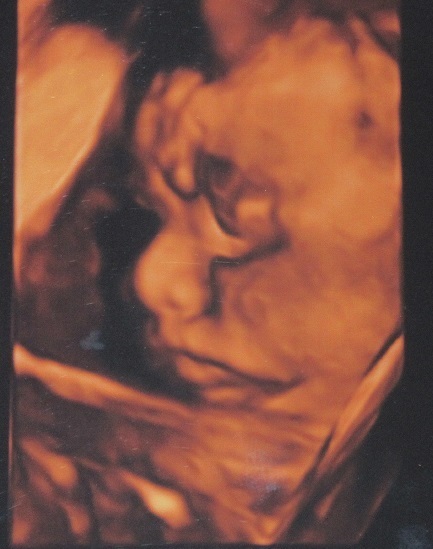

29週1日(29w1d・男の子)|えみこひめ さん(33歳)

エコー写真撮影時のエピソード:

初めて4Dエコーを見たときは、どの写真を見ても同じ顔に見えたのですが、(宇宙人のように思いました)その時々によって笑ったり、しかめっ面をしたりと表情が伝わり、さらにいとおしい存在になりました。

ママ一人だとお顔を見せてくれるのに、パパと一緒にエコーを見たときは恥ずかしいのか手で顔を隠していました!